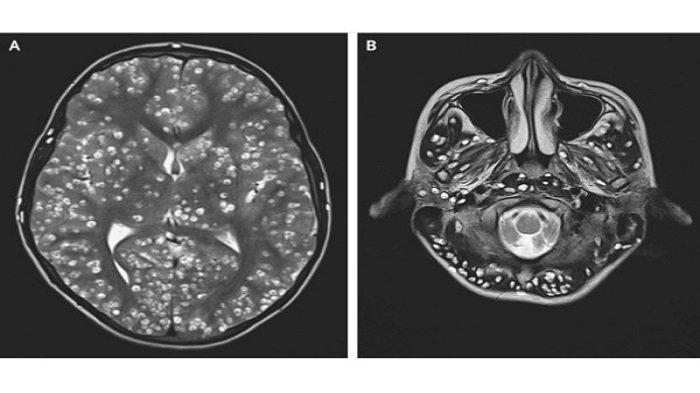

Setelah dilakukan magnetic resonance imaging (MRI), diketahui remaja ini memiliki banyak lesi kistik yang terlihat sangat jelas di seluruh otaknya.

Lesi (jaringan abnormal pada tubuh) ini mirip dengan neurocysticercosis, yang didefinisikan oleh Organisasi Kesehatan Dunia sebagai "infeksi parasit pada sistem saraf pusat dan disebabkan oleh cacing pita babi Taenia solium."